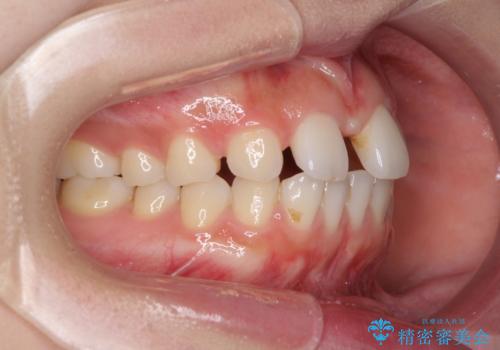

欠損による前歯のスペースが大きかったため、事前にワイヤー矯正で前歯の位置を大きく動かし、その後は上下をインビザラインで整えることとしました。

前歯のスペースは、堅い線維の通った歯肉があり、幅も大きかったことから、歯肉切除を行った上でワイヤー矯正により移動を行いました。また、上唇小帯も歯間部付近まで付着していたため、合わせて切除しました。

ワイヤー矯正により、インビザラインよりも早く、歯軸の向きもコントロールしながら移動させることができました。